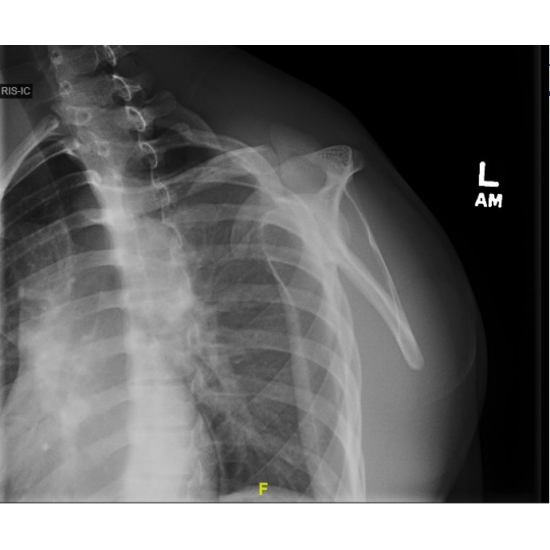

| A Fall To Remember - Page #3 | |||